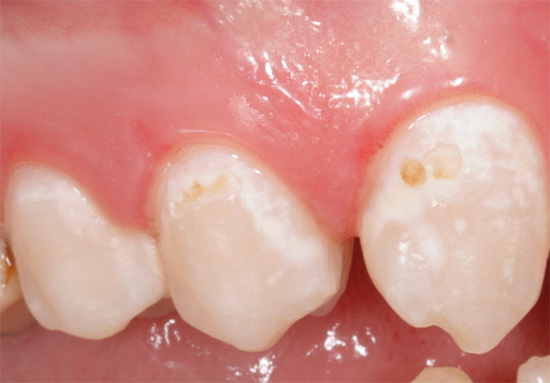

Nella foto sotto, la carie di smalto è presentata come la fase iniziale della lesione con segni caratteristici di questa particolare fase:

Opinione del dentista

Molto spesso puoi osservare lesioni carie nascoste nel campo della fessura. È in queste numerose scanalature che si accumula facilmente la placca, che non può essere spazzolata a lungo. In alcuni casi, il suono di questi pozzi dà immediatamente una risposta, se c'è una rugosità, un difetto nascosto o una demineralizzazione iniziata negli strati sottosuolo.A volte possono esserci sensazioni dolorose a breve termine dal suono, ma il trattamento non può essere avviato senza diagnosi.